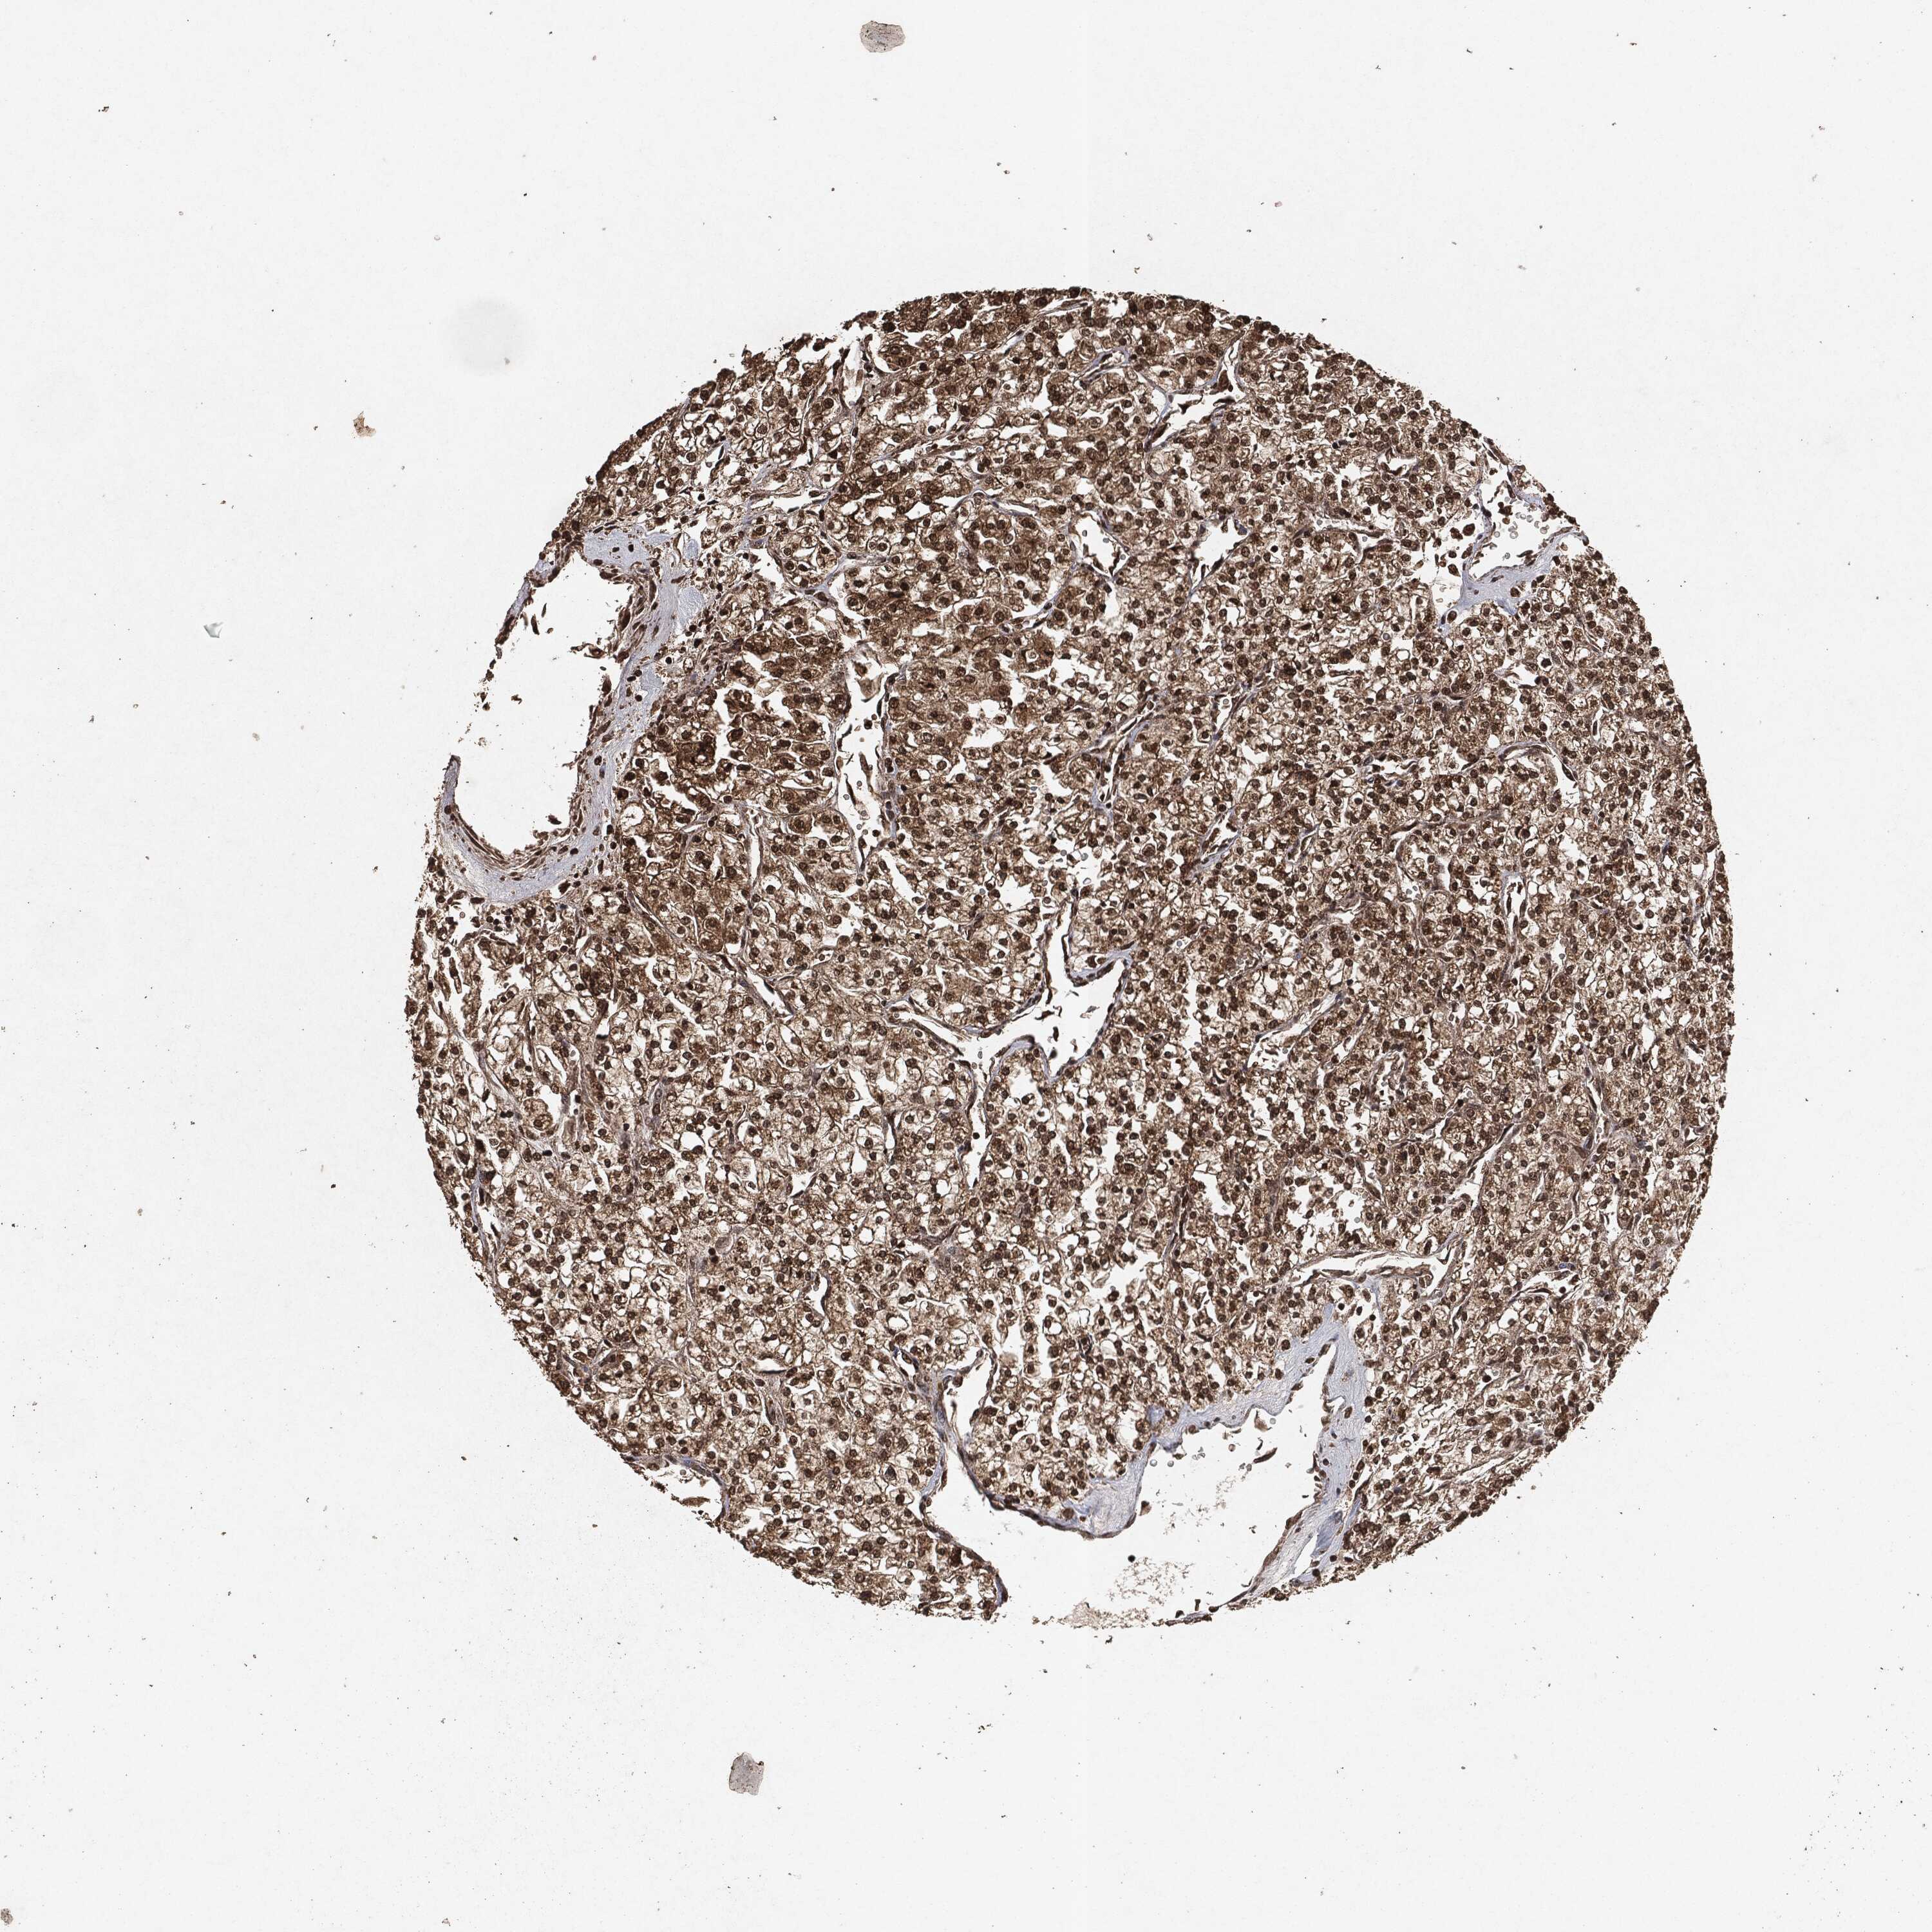

KIDNEY RENAL CLEAR CELL CARCINOMA (TCGA) - Interactive survival scatter ploti

The Survival Scatter plot shows the clinical status (i.e. dead or alive) for all individuals in the patient cohort, based on the same data that underlies the corresponding Kaplan-Meier plots. Patients that are alive at last time for follow-up are shown in blue and patients who have died during the study are shown in red.

The x-axis shows the expression levels (FPKM) of the investigated gene in the tumor tissue at the time of diagnosis. The y-axis shows the follow-up time after diagnosis (years). Both axes are complimented with kernel density curves demonstrating the data density over the axes. The top density plot shows the expression levels (FPKM) distribution among dead (red) and alive patients (blue). The right density plot shows the data density of the survived years of dead patients with high and low expression levels respectively, stratified using the cutoff indicated by the vertical dashed line through the Survival Scatter plot. This cutoff is automatically defined based on the FPKM cutoff that minimizes the p-score. The cutoff can be changed by dragging the vertical line or by entering a cutoff value in the square labeled "Current cut-off".

Under the Survival Scatter plot the p-score landscape (black curve; left axis) is shown together with dead median separation (red curve; right axis). Dead median separation is the difference in median mRNA expression between patients who have died with high and low expression, respectively. It is calculated as follows: median FPKM expression of dead patients with high expression - median FPKM expression of dead patients with low expression. This is intended to aid the user in visually exploring custom cutoffs and the associated p-scores and dead median separation.

Individual patient data is displayed and can be filtered by clicking on one or more of the category buttons on the top of the page. Categories describing expression level and patient information include: high, low, alive, dead, female, male and tumor stages. The scale of the x-axis can be toggled between linear and log-scale by clicking on the "x log" button. Mouse-over function shows TCGA ID, patient information and mRNA expression (FPKM) for each patient.

& Survival analysisi

Kaplan-Meier plots summarize results from analysis of correlation between mRNA expression level and patient survival. Patients were divided based on level of expression into one of the two groups "low" (under cut off) or "high" (over cut off). X-axis shows time for survival (years) and y-axis shows the probability of survival, where 1.0 corresponds to 100 percent.

EGFR is potential prognostic, high expression is favorable in Kidney Renal Clear Cell Carcinoma (TCGA)

Best expression cut offi

Based on the FPKM value of each gene, patients were classified into two groups and association between prognosis (survival) and gene expression (FPKM) was examined. The best expression cut-off refers the FPKM value that yields maximal difference with regard to survival between the two groups at the lowest log-rank P-value. Best expression cut-off was selected based on survival analysis .

When clicking on this number, the vertical dashed line indicating cut-off, the interactive survival plot, and the Kaplan-Meier curve will be adjusted to show results based on the best expression cut-off.

: 29.68

TCGA RNA samplesi

RNA-seq data is reported as average FPKM (number Fragments Per Kilobase of exon per Million reads), generated by the The Cancer Genome Atlas (TCGA) .

Normal distribution across the dataset is visualized with box plots, shown as median and 25th and 75th percentiles. Points are displayed as outliers if they are above or below 1.5 times the interquartile range. FPKM values of the individual samples are presented next to the box plot.

Average pTPM 52.9

Number of samples 521